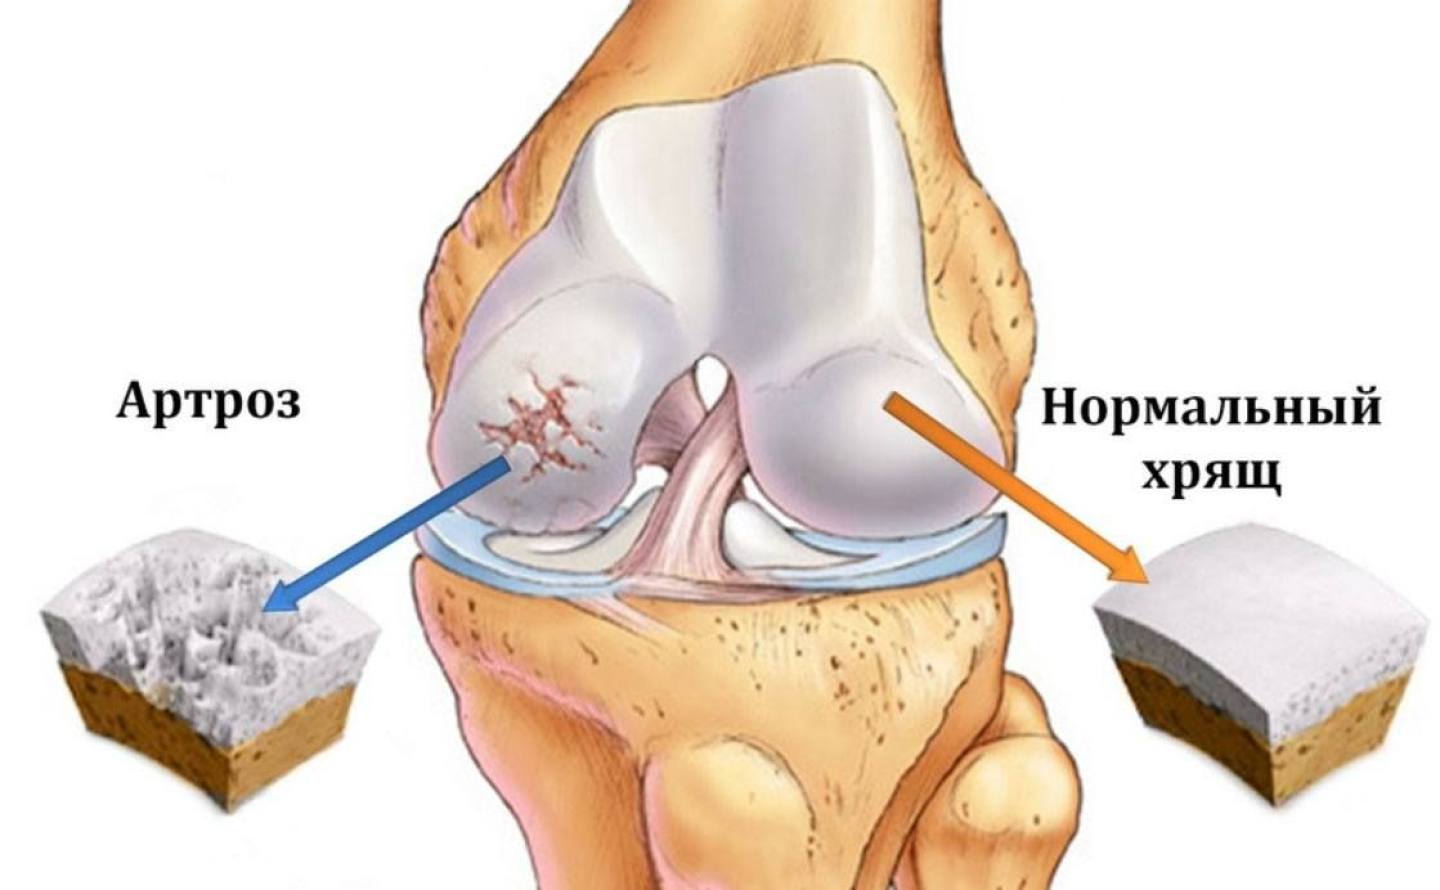

Артроз, коксартроз: симптомы, диагностика, лечение

Артроз, коксартроз: симптомы, диагностика, лечение Артроз – заболевание суставов, при котором прогрессирует разрушение хрящевой ткани. Можно сказать, что артроз…